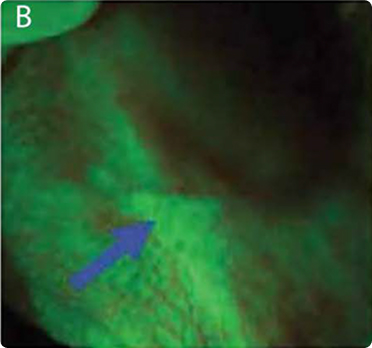

MONITORING TREATMENT SITES WITH VELSCOPE AND DNA PLOIDY: EARLY DETECTION OF RECURRENT ORAL CANCER​

Image A: White-light image of a well-healed scar from squamous cell carcinoma (SCC) on the left lateral tongue.​

Image B: The anterior aspect of the same scar under fluorescence visualization, showing a dark brown area of fluorescence loss.​

Image C: Follow-up after 12 months, with the same area exhibiting a persistent and enlarged loss of fluorescence. After 20 months, a biopsy from the region of fluorescence loss was diagnosed as carcinoma in situ.​